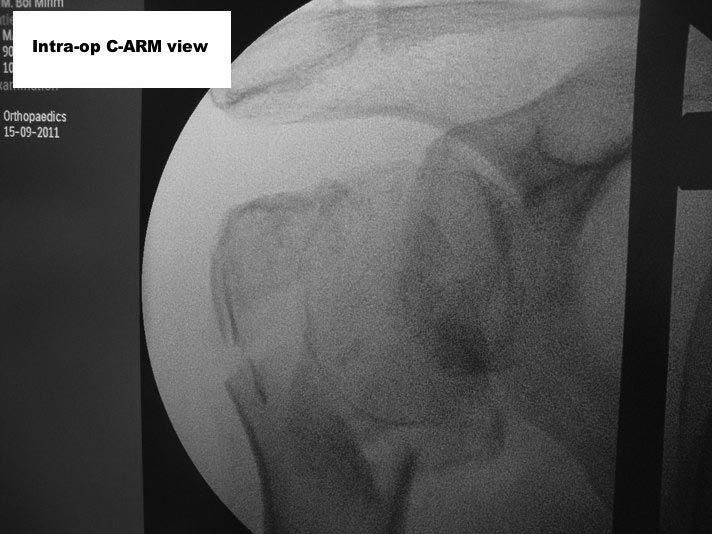

Here are some photos, of chronic, locked, 4 part posterior dislocation, 2 months old, that I did September/2011. Patient is 67, very, very active - had a really reasonable, honest clinical result ...

Photos attached ...